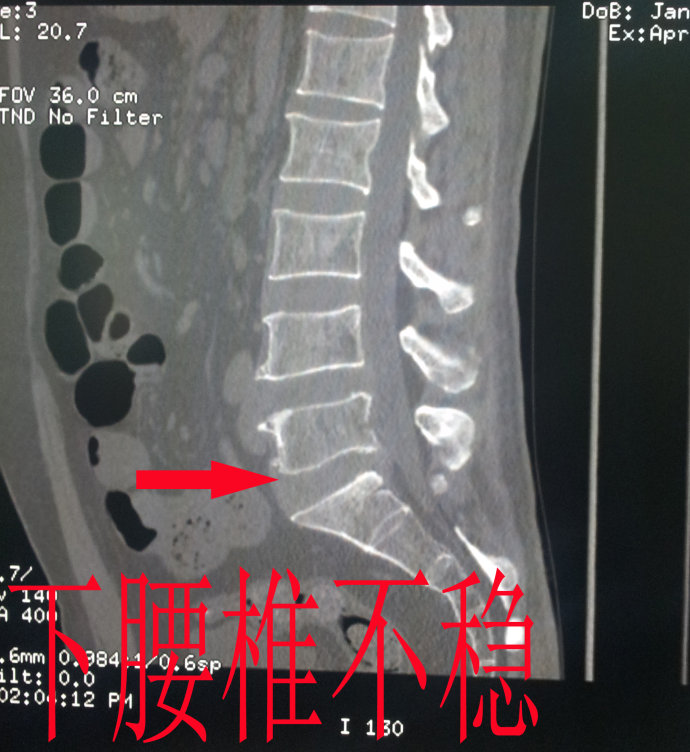

5、腰椎不稳

腰椎的三关节复合体中的椎间盘的后关节退变,不能维持脊柱的稳定,而椎体和关节都会出现增生,最后就会导致纤维性或是骨性强直。所以说腰椎不稳时退变的一个阶段。